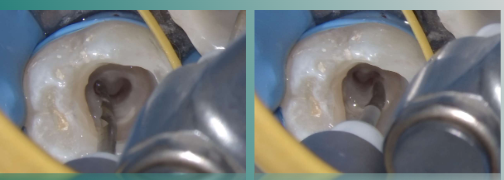

局部黏膜碘伏消毒,4%阿替卡因局部浸润麻醉+牙周膜麻醉下,去尽腐质,远中制作假壁,开髓,揭顶,暴露髓腔。

3%次氯酸钠大量冲洗,清理冠髓,暴露根管口,可见根管呈连续C形。

本病例使用欧罗德卡U系列报管锉进行机械预备

欧罗德卡U系列开口锉1508,去除根管口牙本质领,打开根管中上段,建立直线通路。

10#手用不锈钢器械尖端预弯,测量各根管工作长度,并建立光滑通道。

3%次氨酸钠大量冲洗根管

欧罗德卡U系列通道锉1203对各根管进行疏通,确保通道顺滑,以便后续序列锉进入。